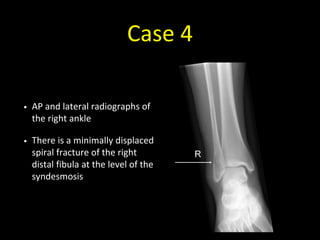

Case 4

• 40 year old with inversion injury of the right ankle

Case 4 - Image 1

Case 4 - Image 2

• AP and lateral radiographs of

the right ankle

• There is a minimally displaced

spiral fracture of the right

distal fibula at the level of the

syndesmosis